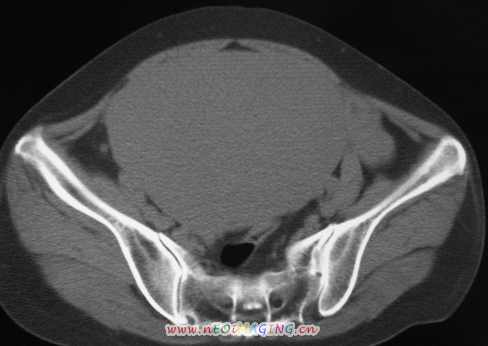

标题: CT11527:女56岁以右输尿管结石入院

女56岁以右输尿管结石入院

支持卵巢囊腺瘤;右侧输尿管第二狭窄处结石伴梗阻。

1)盆腔占位性病变,考虑来源于卵巢,囊腺瘤可能性大。2)右侧输尿管第二狭窄处结石伴梗阻。

今天病人已经手术证实为右附件囊肿,右侧输尿管第二狭窄处结石伴梗阻!!!

[病理诊断] CT11527:右附件囊肿,右侧输尿管结石。